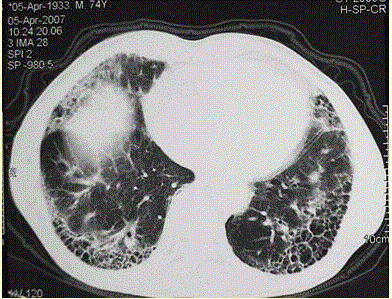

问题 患者男,73岁。进行性呼吸困难半年,加重2个月。否认吸烟史、粉尘接触史。查体:发绀,杵状指,双肺底闻爆裂音。血常规正常,ERS 16 mm/h。胸部CT 如图所示。 最可能的诊断是

选项 A.COPD B.UIP C.肺部感染 D.支气管扩张症 E.NSIP

答案 B